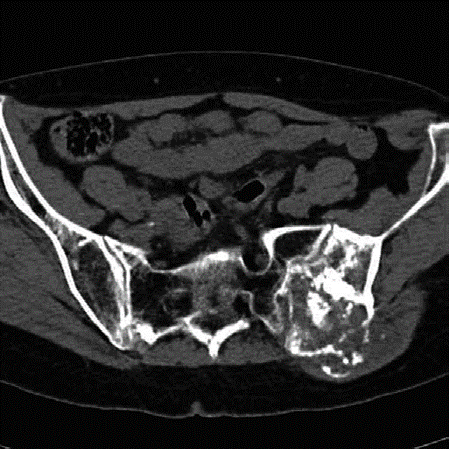

Lower limb Trauma Structured oral examination question 1 A 35-year-old motorcyclist came off his bike yester-…